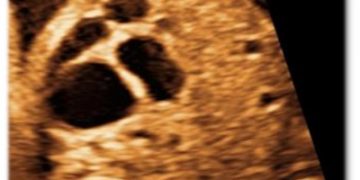

Cari soci, finalmente online le soluzioni dei casi del mese di Luglio Grazie a Carlotta Zorzi e Daniele Di Mascio!! Caso 1 - video [pdf-embedder url="https://www.sieog.it/wp-content/uploads/2024/07/risposta-Casodelmese_Luglio20241.pdf" title="risposta...